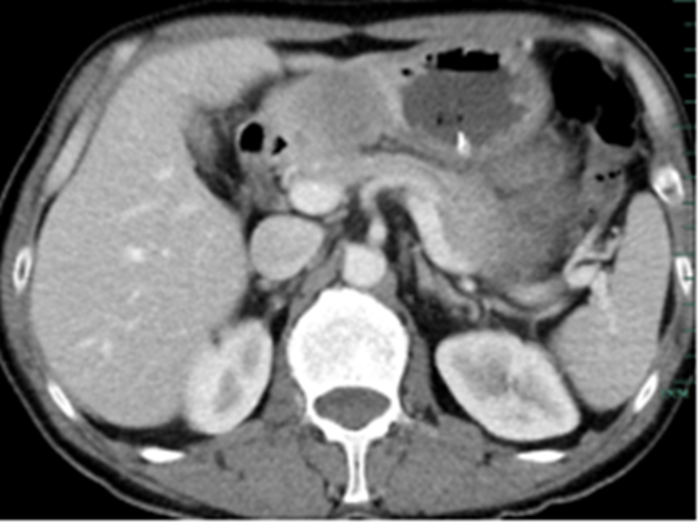

住院后經(jīng)胸腹部CT檢查,提示周先生胃部巨大腫塊穿破胃腔,可能累及到結(jié)腸,同時合并有胃旁淋巴結(jié)轉(zhuǎn)移、肝臟的轉(zhuǎn)移??吹竭@個檢查報告后,周先生和他的愛人一下子就泣不成聲了。

治療前的腹部CT提示胃